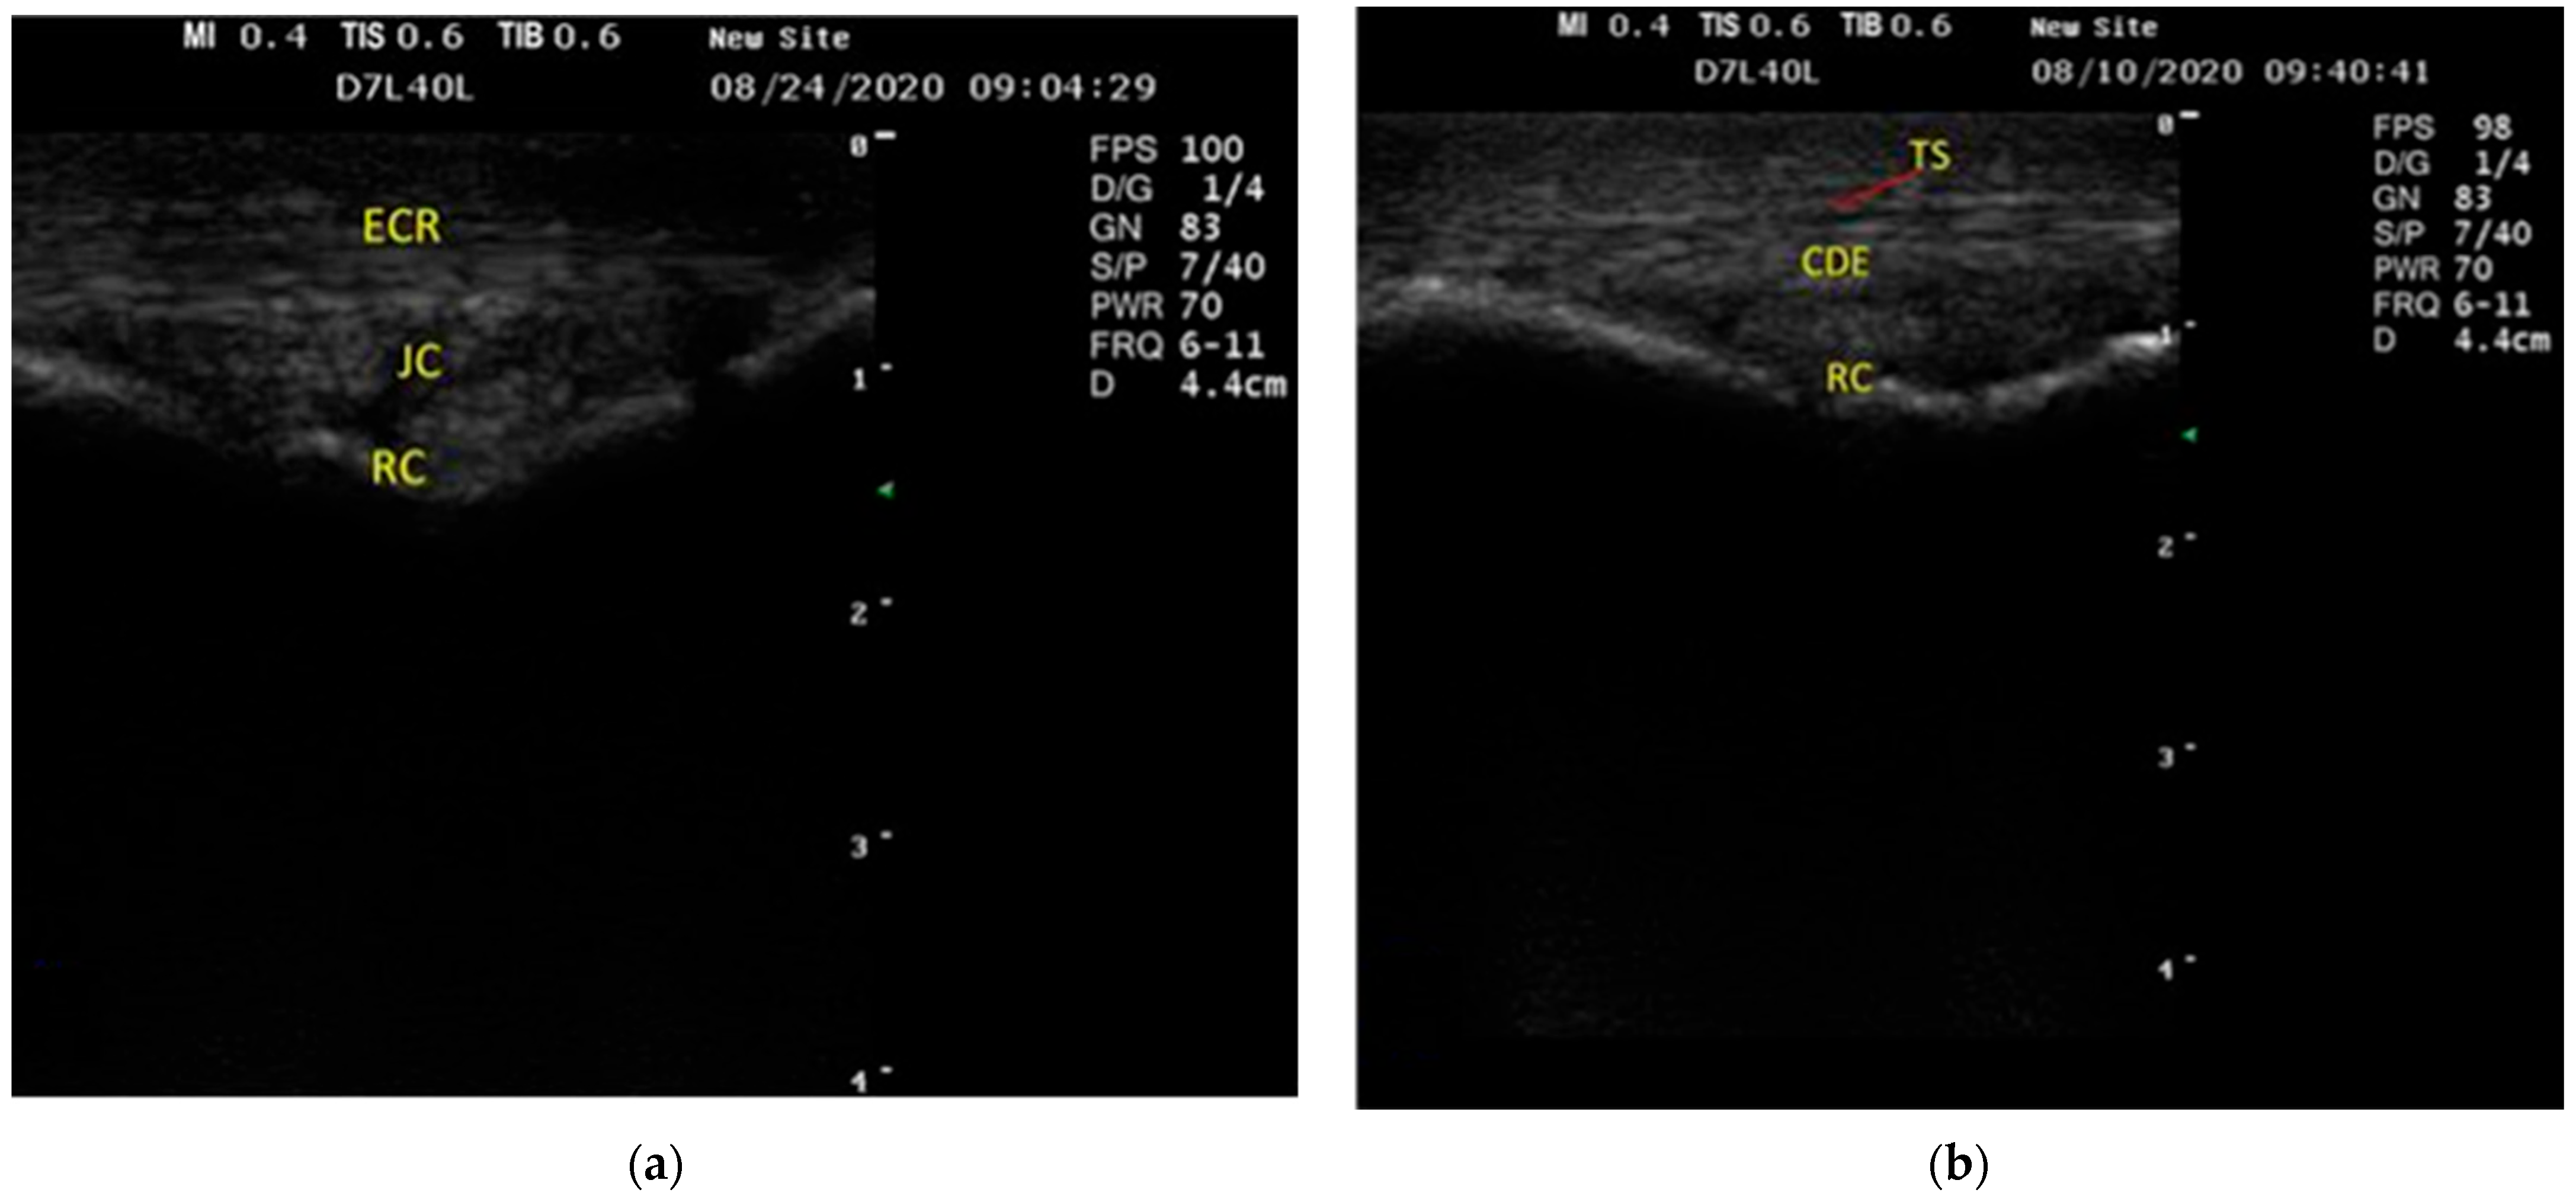

3.1. US Findings